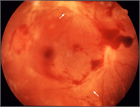

病態

1. 角膜、水晶体、中間透光体、眼底のみならず視神経から後頭葉に及ぶ視路を障害する疾患で視力低下が起こり得る。